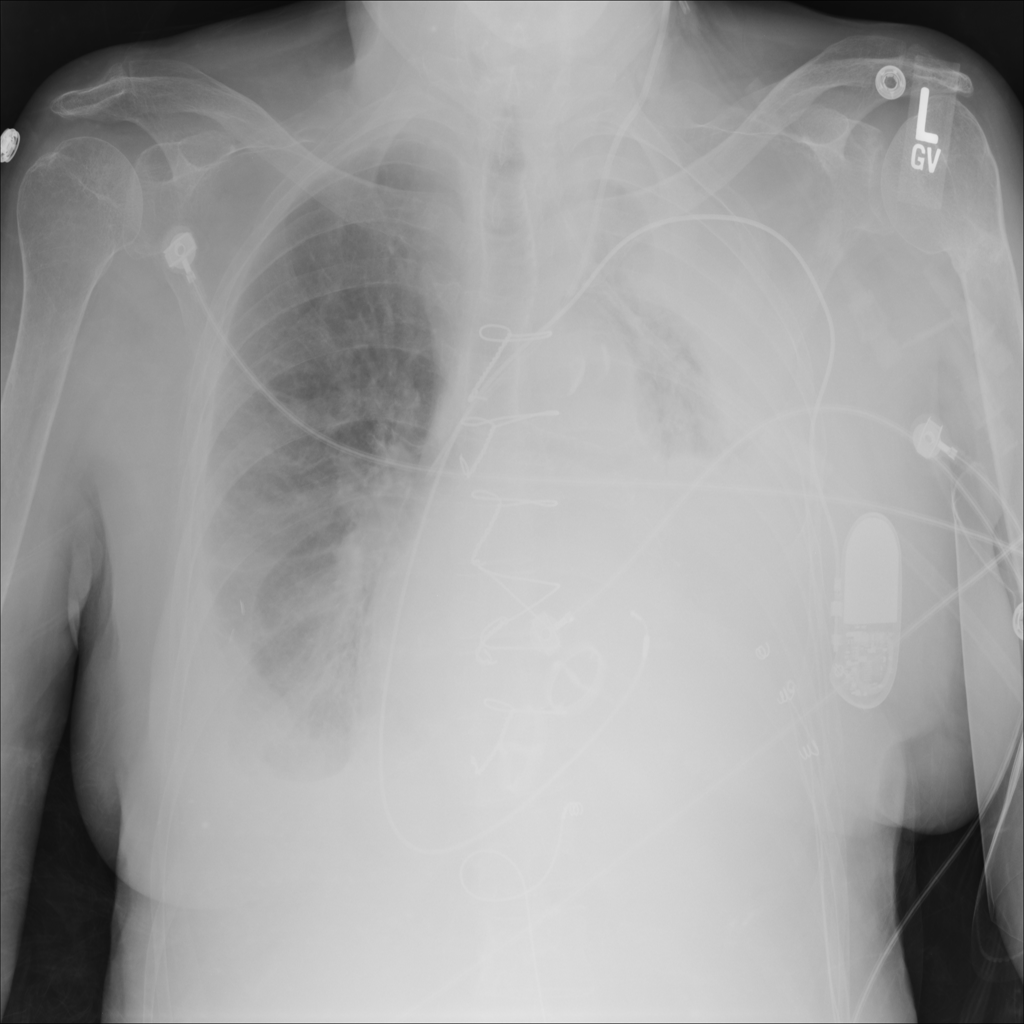

PAT-E81B · IMG-000Effusion

PAT-E81B · IMG-000

PA